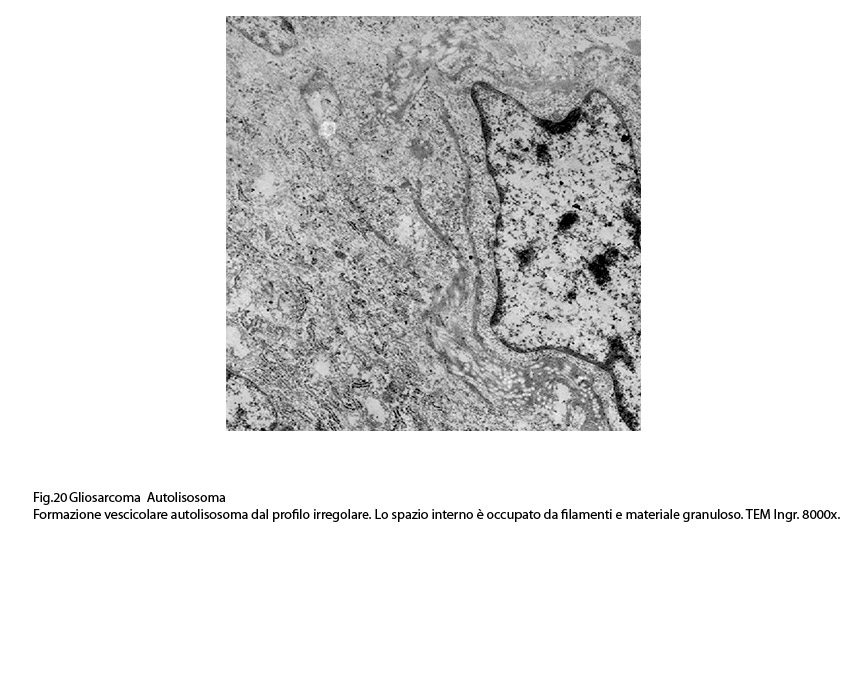

Dopo questa fase di accumulo del cargo,segue quella della fusione tra l’autofagosoma e un lisosoma con formazione di una nuova struttura indicata con il termine di autolisosoma.

Gli autolisosomi inizialmente mostrano una doppia membrana di contorno,successivamente la membrana interna viene demolita dagli enzimi lisosomiali e appaiono come sub strutture vescicolose delimitate da una membrana a monostrato; pertanto si distinguono con difficoltà dai lisosomi secondari.(Margit Pavelka, Jurgen Roth: Functional Ultrastructure,Springer Verlag, 2015).

Nel citoplasma delle cellule di gliosarcoma esaminate sono stati riscontrati con frequenza focolai di autofagosomi e di autolisosomi; i primi si riconoscono quali corpi ovoidali o rotondeggianti i quali sono demarcati da una membrana a doppio contorno e contengono nel loro spazio cavo materiale granuloso,filamentoso ed amorfo; i secondi,gli autolisosomi, sono delimitati da una membrana a monostrato,spesso notevolmente ispessita per sovrapposizione di materiale amorfo;il loro contenuto è rappresentato da materiale biologico in varie fasi di degradazione.

Fig.20  Fig.21